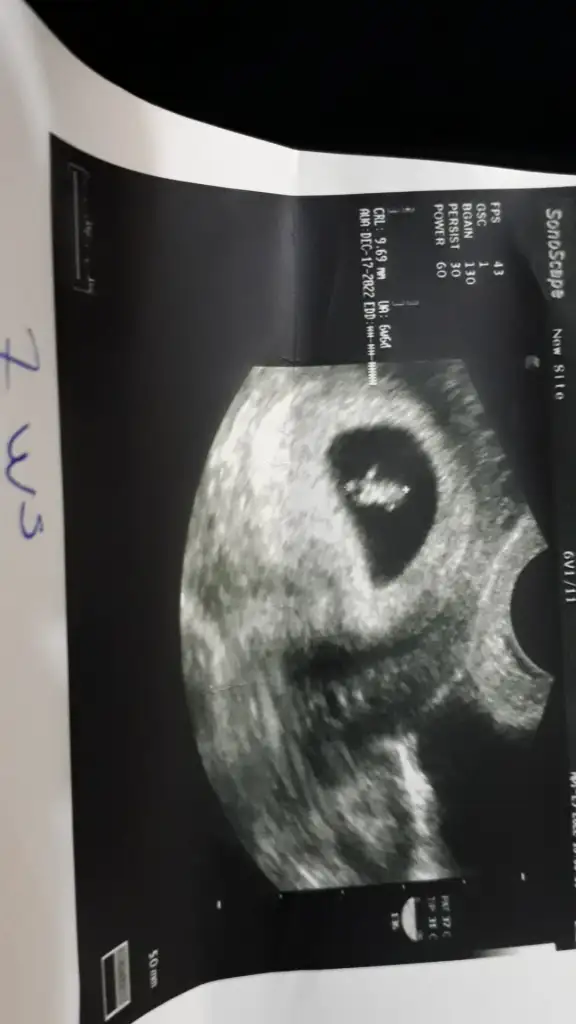

hayırlısı olsun benimde en son 8+5 resmim bu yeterki sağlıklı koşunlarda insan yine de merak ediyor teşekkür ederim